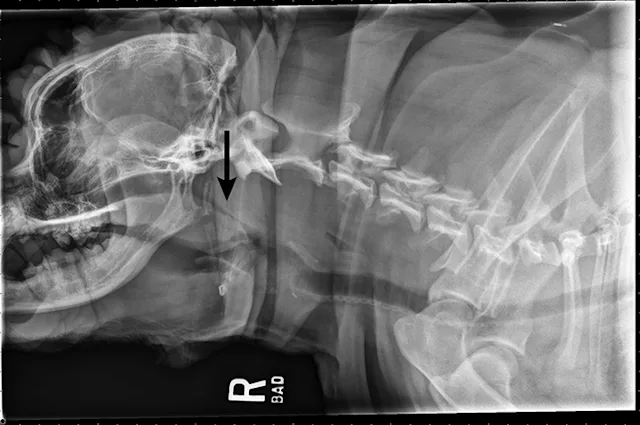

Thoracic radiographs reveal a mildly hypoplastic trachea and no evidence of aspiration pneumonia (Figure 1). A lateral cervical radiograph shows an elongated, thickened soft palate partially obstructing the laryngopharynx and nasopharynx (Figure 2). Airway examination confirmed the elongated soft palate obstruction and tonsillar eversion (Figure 3). Everted laryngeal saccules are also present. Brachycephalic obstructive airway syndrome (BOAS) is diagnosed. Folded flap palatoplasty, laryngeal sacculectomy, and alarplasty are recommended after improvement in airway swelling associated with the acute episode.